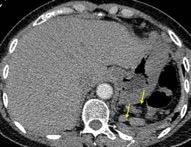

Síndrome de afectación postcardiaca (postcardiac injury)

Post infarto 1-7 % (Dressler)

Trauma cerrado Implantación marcapasos

Cirugía cardiaca. 17-31% (Post.pericardiotomía)

3707 pacientes 29 Derrames (0,78%) > de 25% del hemitórax

Todas menos 2 Izdos.

Angioplastia

By-pass coronario 21-10-03